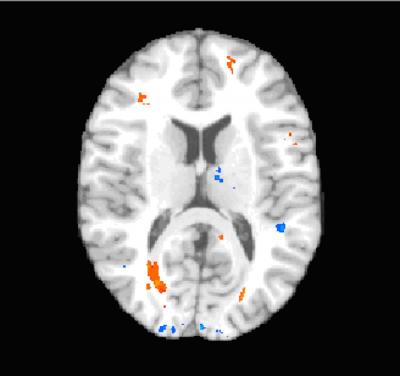

Patients and controls also underwent diffusion tensor imaging (DTI), a recently developed MRI-based imaging technique that can detect subtle changes in the brain by measuring the diffusion of water in the brain's white matter. DTI revealed abnormal brain regions in 15 of the concussion patients, while no abnormal regions were found in controls. Most importantly, the presence of major areas of structural damage in concussion patients (as shown by large alterations in normal water diffusion using DTI) predicted low scores on their executive-function tests. These damaged areas were located mainly in the brain's prefrontal cortex, which is essential for normal executive function and is susceptible to injury in concussion.

Dr. Lipton notes that use of DTI could prompt doctors to begin treatment early, when it's likely to be most useful. "The problems in functioning caused by concussions often don't become evident until weeks or months after the injury, suggesting that the brain pathology may actually expand over time," he notes. "By detecting brain injury early with DTI and then initiating cognitive rehabilitation therapies for those patients, we may be able to limit the effects of concussions."